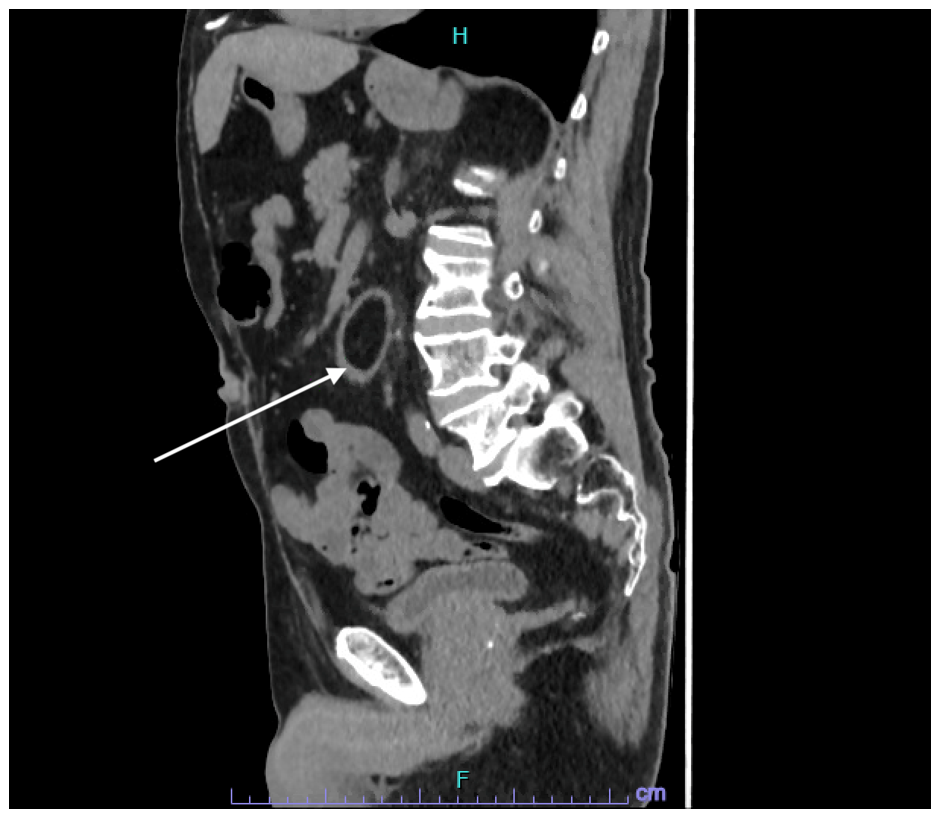

| Figure 3: Computed tomography of the abdomen- sagittal section. Duodenal lipoma is indicated with an arrow |

Computed tomography (CT) of the abdomen confirmed the presence of a duodenal lipoma extending from the 2nd to 4th part of the duodenum, measuring 95 mm x 30 mm (Figure 1 - 3).

Computed tomography (CT) has grown in popularity for diagnostic purposes in the last decade. Lipomas are easily and reliably identified on CT because of their appearance as a smooth margined mass combined with a characteristic low uniform (fat density) attenuation with a low Hounsfield Unit (HU) count from -70 to -120 HU [28-30].